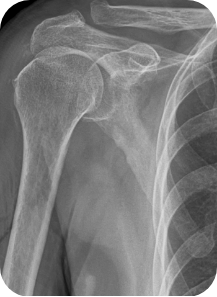

회전근개 질환, 오십견, 어깨 탈구 등 어깨 질환은 어깨의 통증과 고통을 야기합니다. 어깨 관절내시경 수술은 관절 질환이 의심되는 부위를 1cm 미만으로 최소절개한 뒤, 내시경 카메라와 수술 기구를 관절 내부에 삽입해 질환을 진단하고 치료하는 수술입니다. 화면을 통해 병변 부위를 직접 확인할 수 있어 손상 정도에 따라 파열된 힘줄을 봉합하거나 염증을 제거할 수 있습니다. CT나 MRI 등의 진단으로 잘 보이지 않던 곳까지 내시경을 삽입할 수 있어 적용 범위가 점점 넓어지고 있는 추세입니다.

- 회전근개 질환이 있는 경우

- 오십견, 어깨충돌증후군이 있는 경우

- 어깨탈구가 습관성으로 일어날 경우